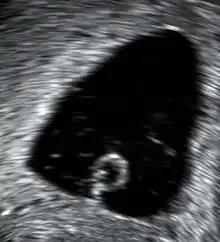

In the case of blood loss, pain, or both, transvaginal ultrasound is performed. If a viable intrauterine pregnancy is not found with ultrasound, blood tests (serial βHCG tests) can be performed to rule out ectopic pregnancy, which is a life-threatening situation.[94][95]

A miscarriage may be confirmed by an obstetric ultrasound and by the examination of the passed tissue. When looking for microscopic pathologic symptoms, one looks for the products of conception. Microscopically, these include villi, trophoblast, fetal parts, and background gestational changes in the endometrium. When chromosomal abnormalities are found in more than one miscarriage, genetic testing of both parents may be done.[96]